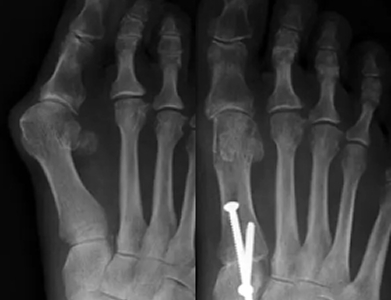

An osteotomy can be performed for other conditions, not just bunions. The term osteotomy refers to any surgery where bones are reshaped, but when talking about bunions, an osteotomy is performed to remove a bit of bone to help realign the toe and support the joint. Typically, pins and screws will be used to support the newly aligned bone and to keep the toe straight.

An exostectomy is the surgery to remove the bony bump that defines the bunion. This surgery is often just one part of the bunion surgery and is paired with soft tissue procedures and a technique to straighten the toe and support joint health. Removing the bunion lump alone will not solve the problem. As you can see from x-rays, bunions include significant shifts in how the toe bone lies. To fully solve a bunion, other steps must be taken to straighten the toe.